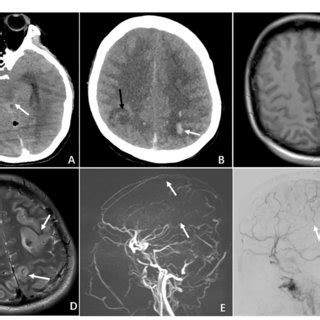

FIGURE E Radiographic features of CVT in the ca...